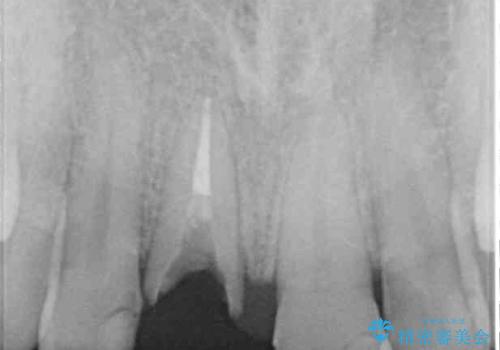

診察の結果、前歯が縦に破折しており、抜歯が必要と診断されました。

補綴治療としては、インプラントあるいはブリッジの2つがありますが、患者様と相談した結果、インプラントによる補綴治療を選択することとなりました。

咬合力が非常に強いため、インプラントにも過度な力の負担が発生する恐れがあります。